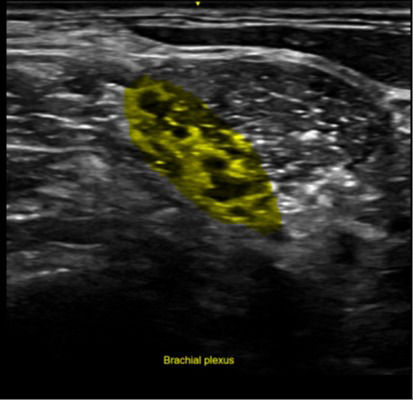

AI assists in ultrasound-guided nerve blocks

During the scouting phase, use cNerve to identify the nerve landmark and see it highlighted on the image. This helps detect and track the nerve in 99% of cases while scanning or reviewing a stored clip.¹